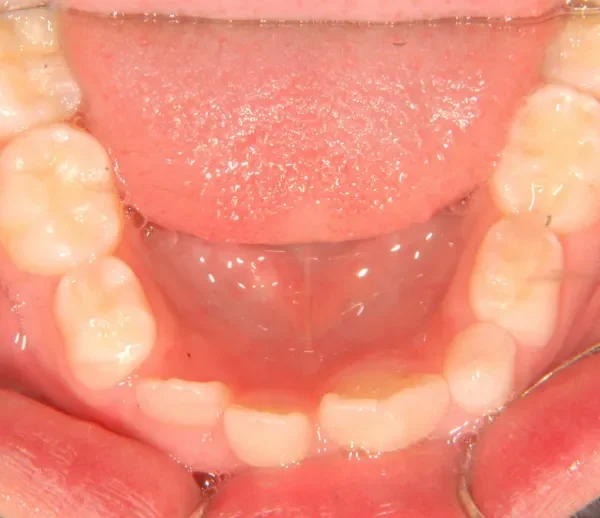

初診時年齢 小学校2年生 (男性) 主訴 癒合歯・永久歯が生えるスペースがない

診断名 叢生 装置名

状態 永久歯が生える隙間がない(叢生)

ガタガタ・でこぼこに生えている(叢生)

上下の歯並びが狭く、永久歯の生える隙間がありません。

右下に癒合歯があり 上下の歯並びのアーチが悪くなっています。

初診